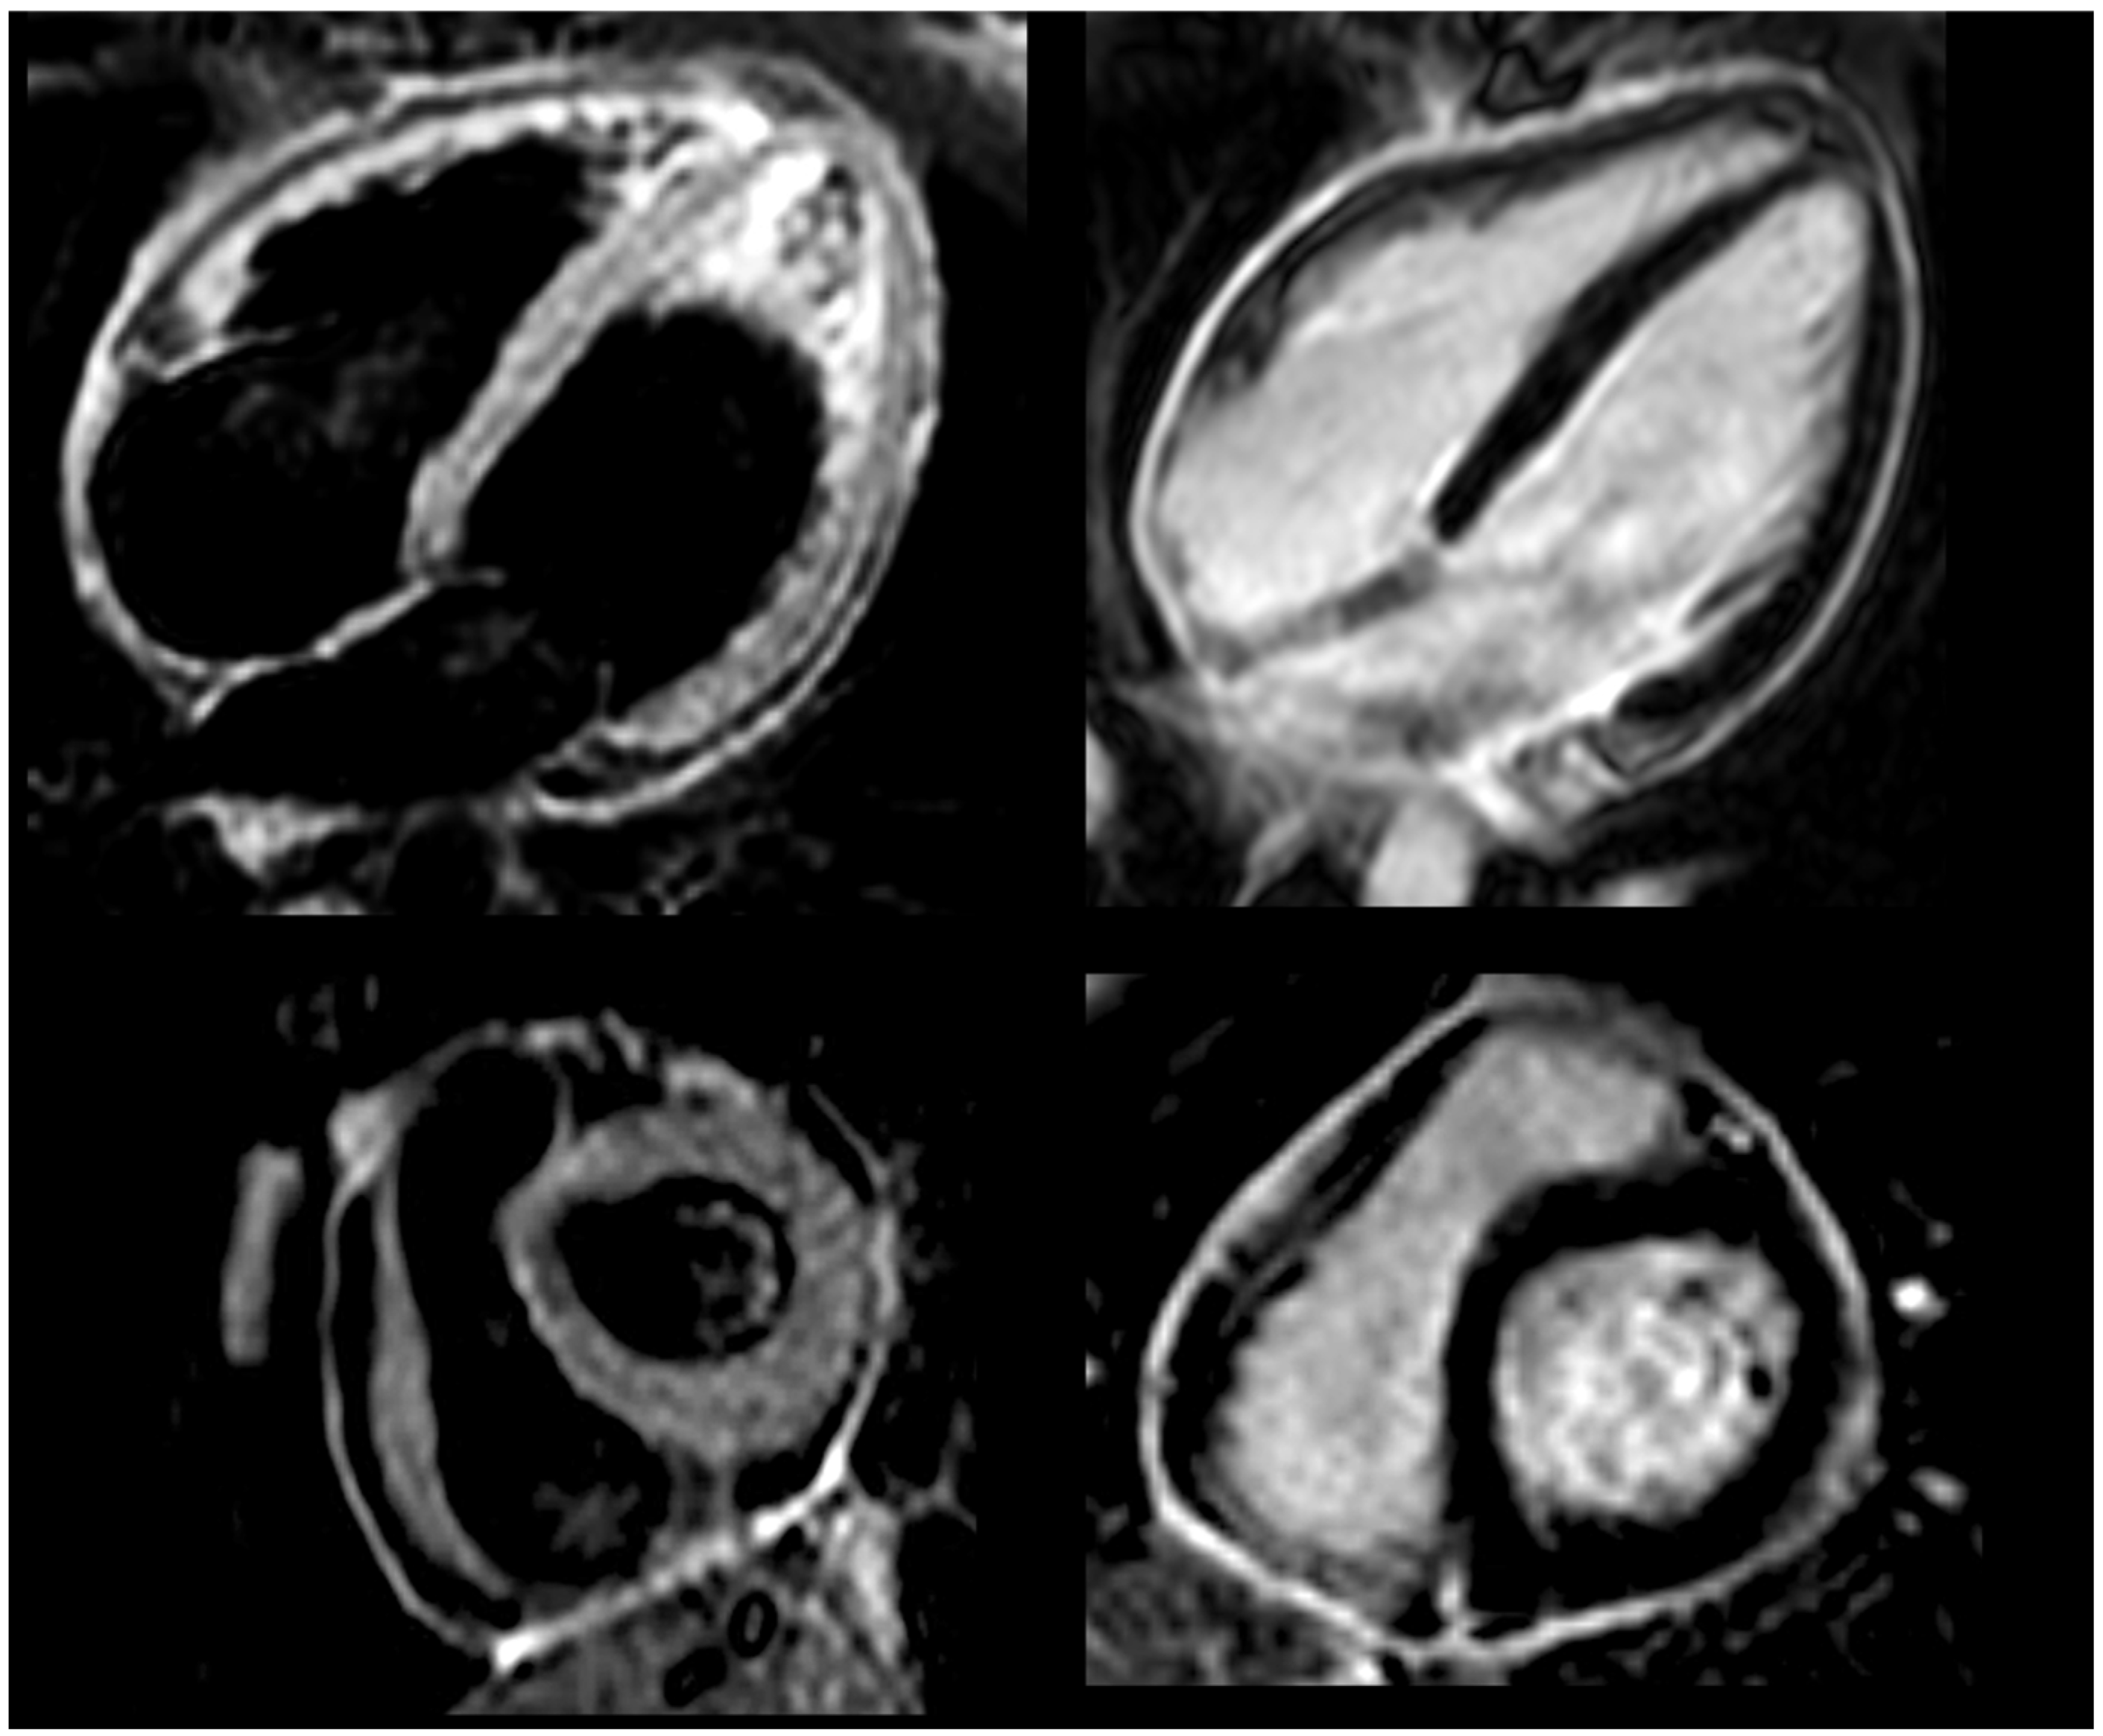

2.2. Current Assessment and Differential Diagnosis